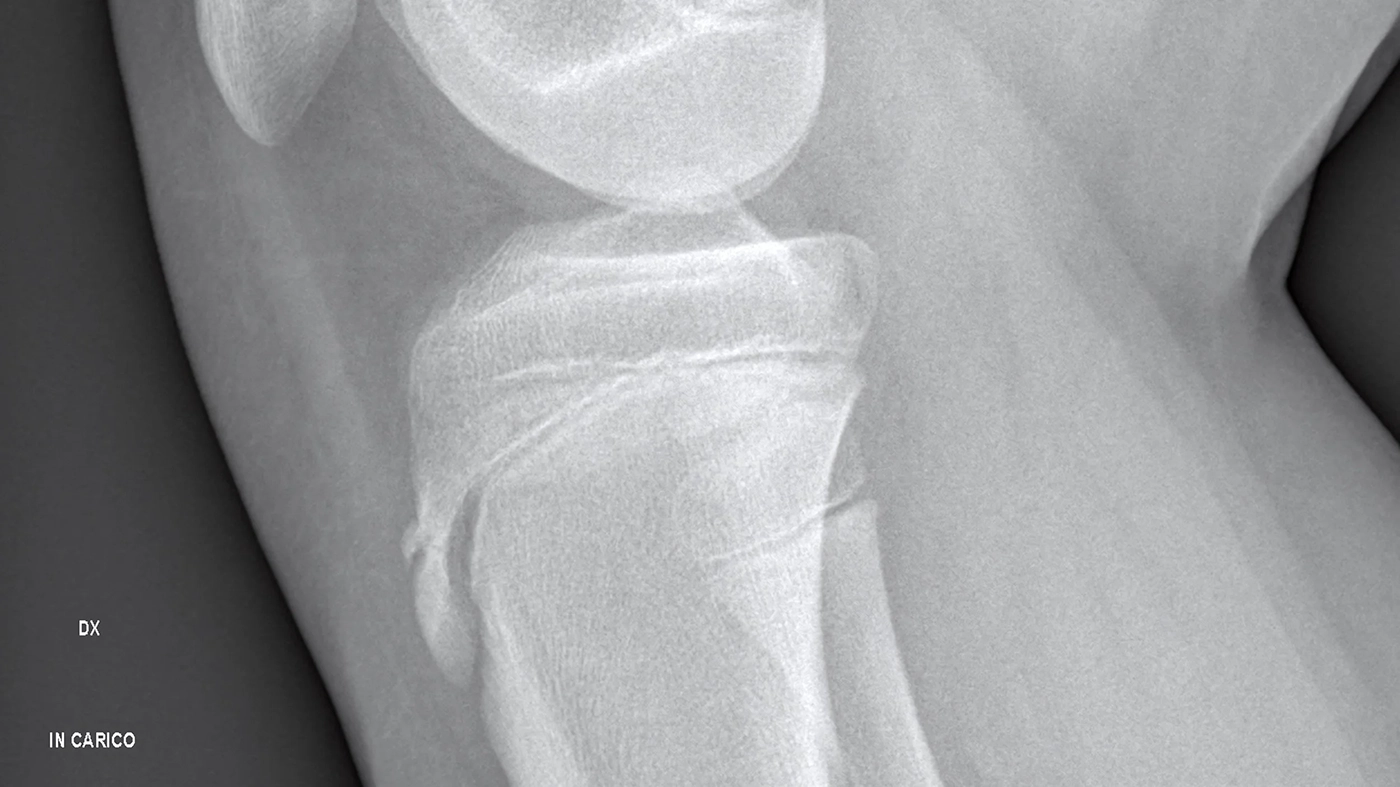

Osgood-Schlatter’s Disease: Understanding Knee Pain in Active Kids and Teens in Sarasota

If your child or teen is active in sports around Sarasota—from soccer and track to dance or baseball—and suddenly starts complaining of pain just below the kneecap, they may be experiencing a common growth-related condition known as Osgood-Schlatter’s disease. At Vertical Chiropractic® Sarasota, we see …